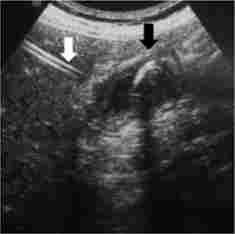

Мал. 28.6. Черезшкірна чреспеченочная холецістостомія:

біла стрілка - неробоча частина дренажу встановлена траспеченочно; чорна стрілка - фіксує кільце встановлено в просвіті жовчного міхура

Показаннями до дренування просвіту жовчного міхура (рис. 28.6) виступають такі стани:

Причиною гострого холециститу в переважній більшості випадків виявляється жовчнокам'яна хвороба з вклиненням конкременту в області шийки жовчного міхура.

Механічна жовтяниця, при якій визначаються ознаки блокує

ванного жовчного міхура, може бути викликана наступними причинами; конкременти, пухлина або стриктура загальної жовчної протоки; пухлини головки підшлункової залози або метастатична поразка лімфатичних вузлів гепатодуоденальной зв'язки.